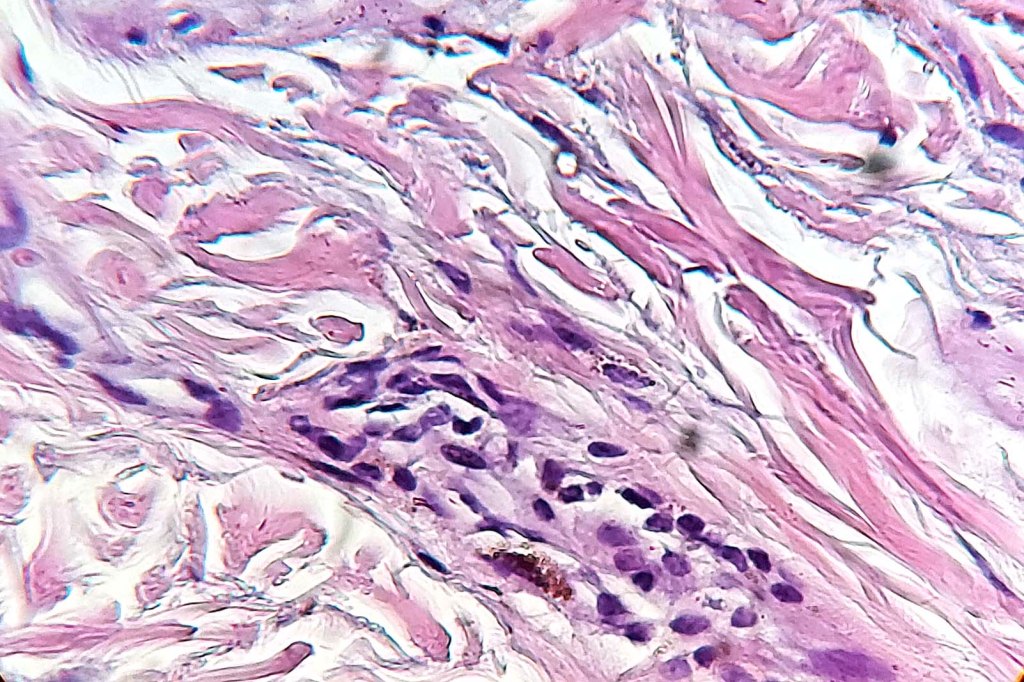

Histologically the features are very subtle and may require a Masson Fontanna stain or immunohistochemistry for diagnosis. Small numbers of dendritic melanocytes are present in the deep dermis siad to be orientated parallel to the epidermis.

Histologically, both lesions are characterized by the presence of denritic melanocytes in the upper & mid dermis. The overlying epidermis is often hperpigmented and increased numbers of melanocytes are sometimes evident.

Histologically, it is characterized by a dense population of spindled, dendritic melnanocytes & melanophages with variable fibrosis. It may sometimes represent a component of a combined nevus. Mitotic activity is not usually present and pleomorphism is absent (see atypical blue nevus below). Involvement of the arrector pili muscle is not uncommon.

•Some tumors are composed spindle cells in a fascicular or neuronevoid pattern

•Desmoplastic variant